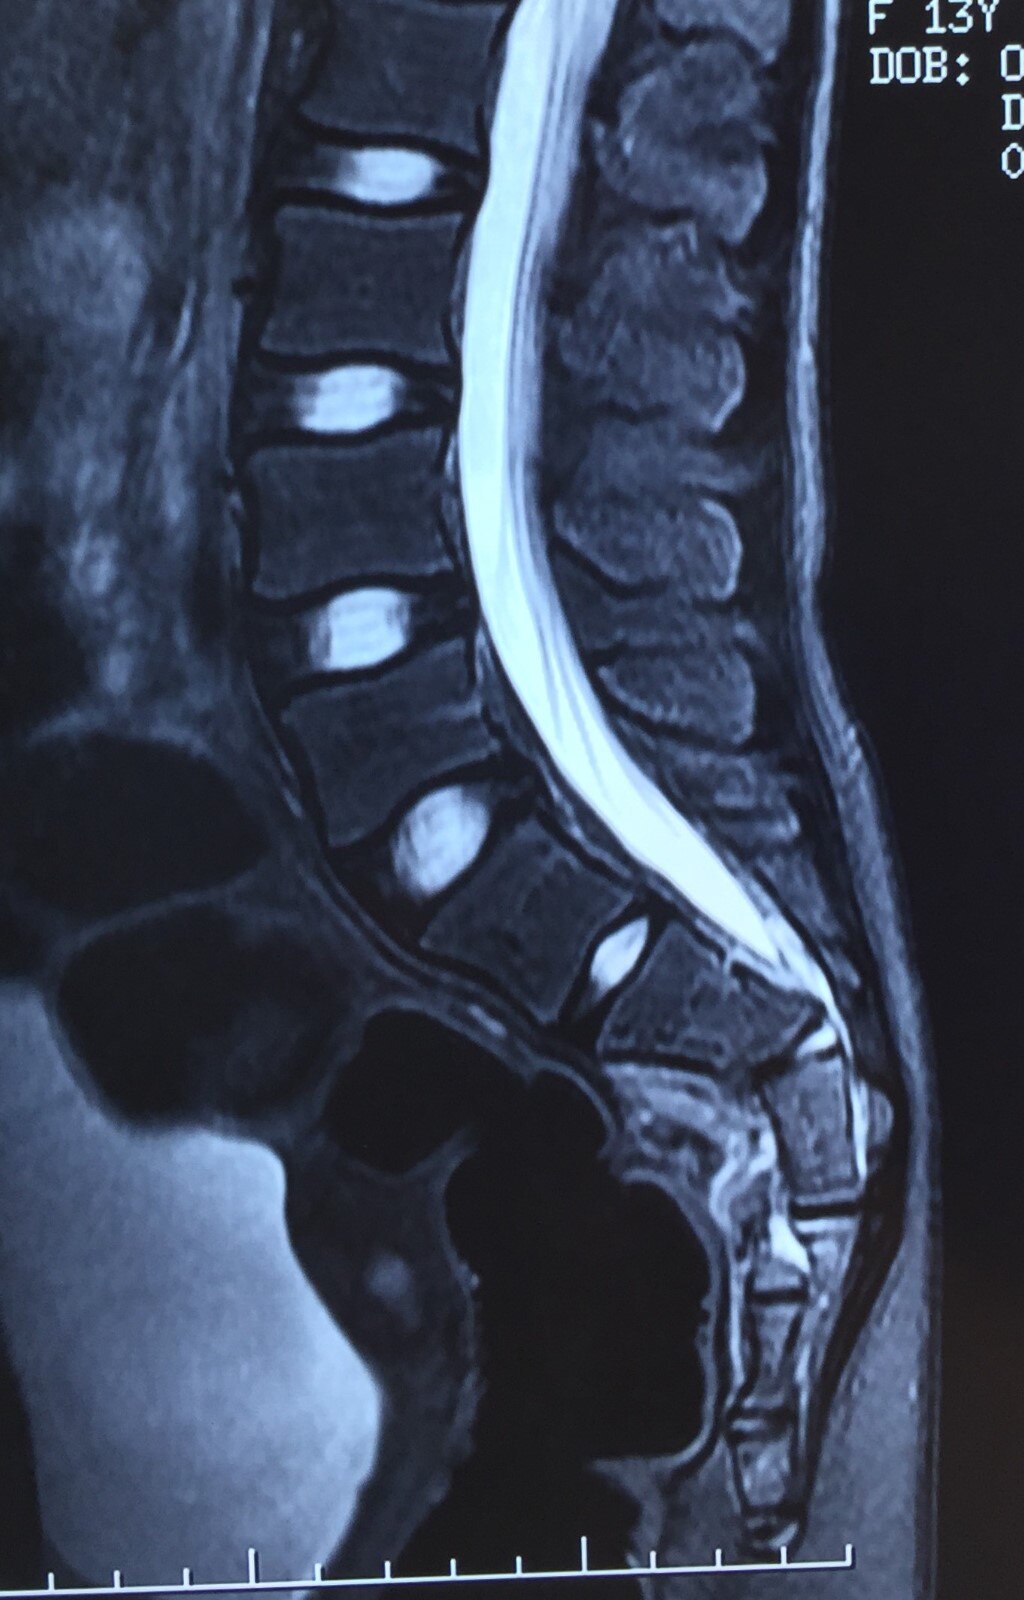

骶5椎体可见骨皮质断裂,骨折端稍移位.余骶尾椎未见异常.怎么办?